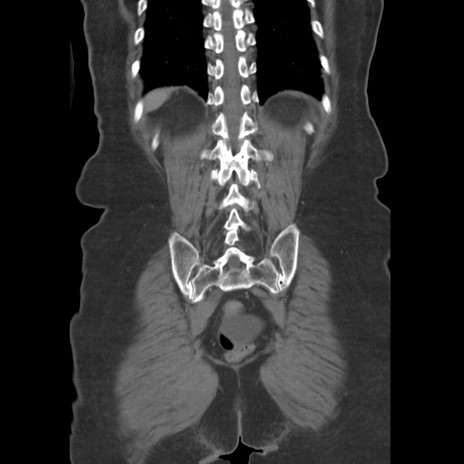

症例19(冠状断像)

【症例】80歳代女性

【主訴】下腹部痛

【現病歴】約8時間前より下腹部痛の出現あり、救急外来受診。

【既往歴】両側付属器切除

【身体所見】意識清明、下腹部正中に手術痕あり、その部位に一致して圧痛と反跳痛あり。腸蠕動音は亢進。

【データ】WBC 9300、CRP 0.15